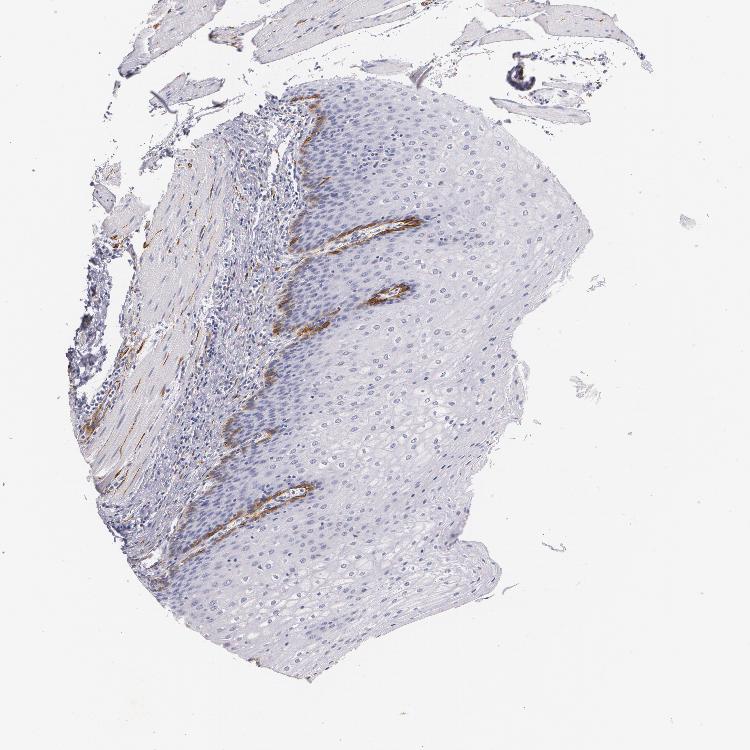

ESOPHAGUS - Antibody stainingi

Antibody staining in the annotated cell types in the current human tissue is reported as not detected, low, medium, or high, based on conventional immunohistochemistry profiling in selected tissues. This score is based on the combination of the staining intensity and fraction of stained cells.

Each image is clickable and will lead to virtual microscopy that enables deeper exploration of all samples and also displays staining intensity scores, fraction scores and subcellular localization as well as patient and tissue information for each sample.

Antibody HPA004765Antibody CAB000143Antibody CAB001995

Squamous epithelial cells MediumMediumLow